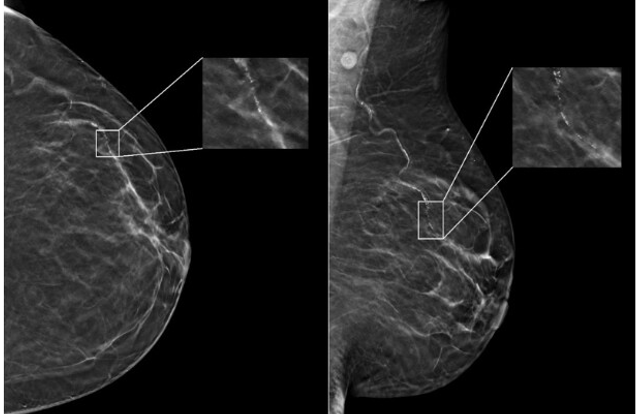

In Week 21’s “Let’s Talk AI,” discover how artificial intelligence helps airlines optimize their flight operations. Learn more about an AI-driven study revealing differences in brain structures between men and women. Plus, get to know DEPLOY, an AI tool capable of classifying brain tumors into 10 major subtypes with 95% accuracy.